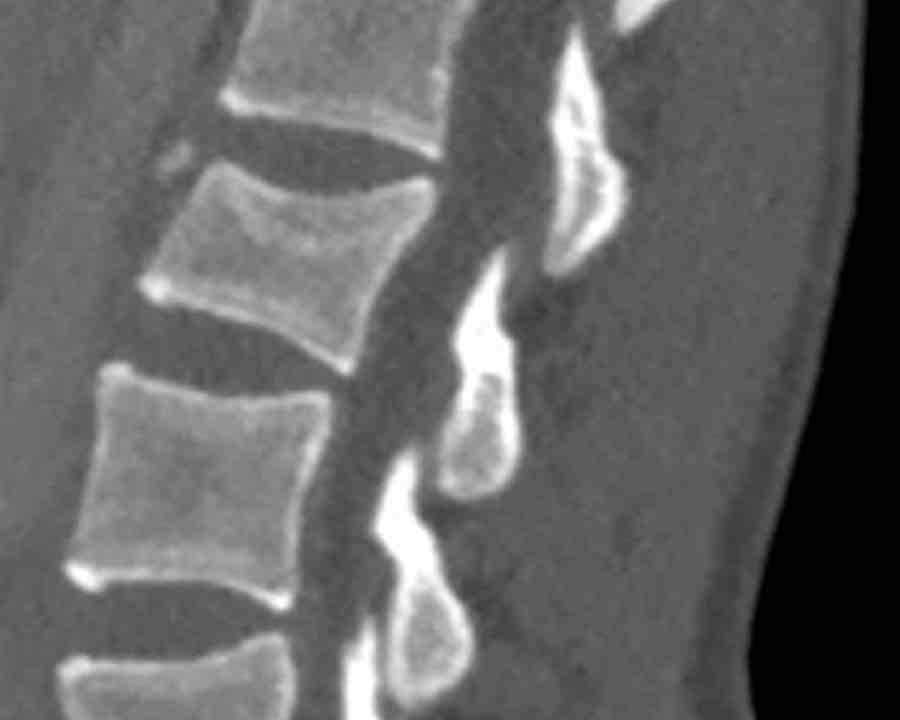

A3 Incomplete Burst fractures

Fracture with any involvement of the posterior wall; only a single endplate fractured.

A vertical fracture of the lamina is usually present and does not constitute a tension band failure.

Findings:

- No C or B injury

- Fractures vertebral body with involvement of upper endplate (1 point) and posterior wall (2 points)

Conclusion

Injury type A3